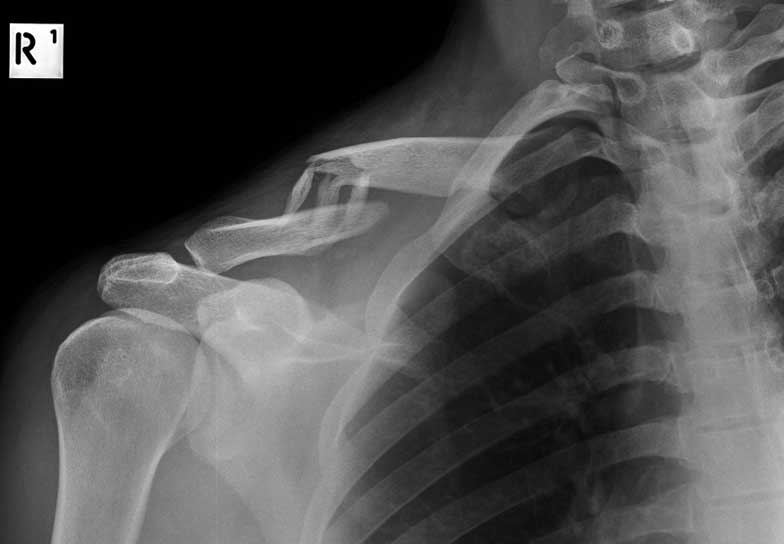

What do Distal Clavicle Fractures Look Like on X-ray and CT?

X-RAY

Click an image to enlarge